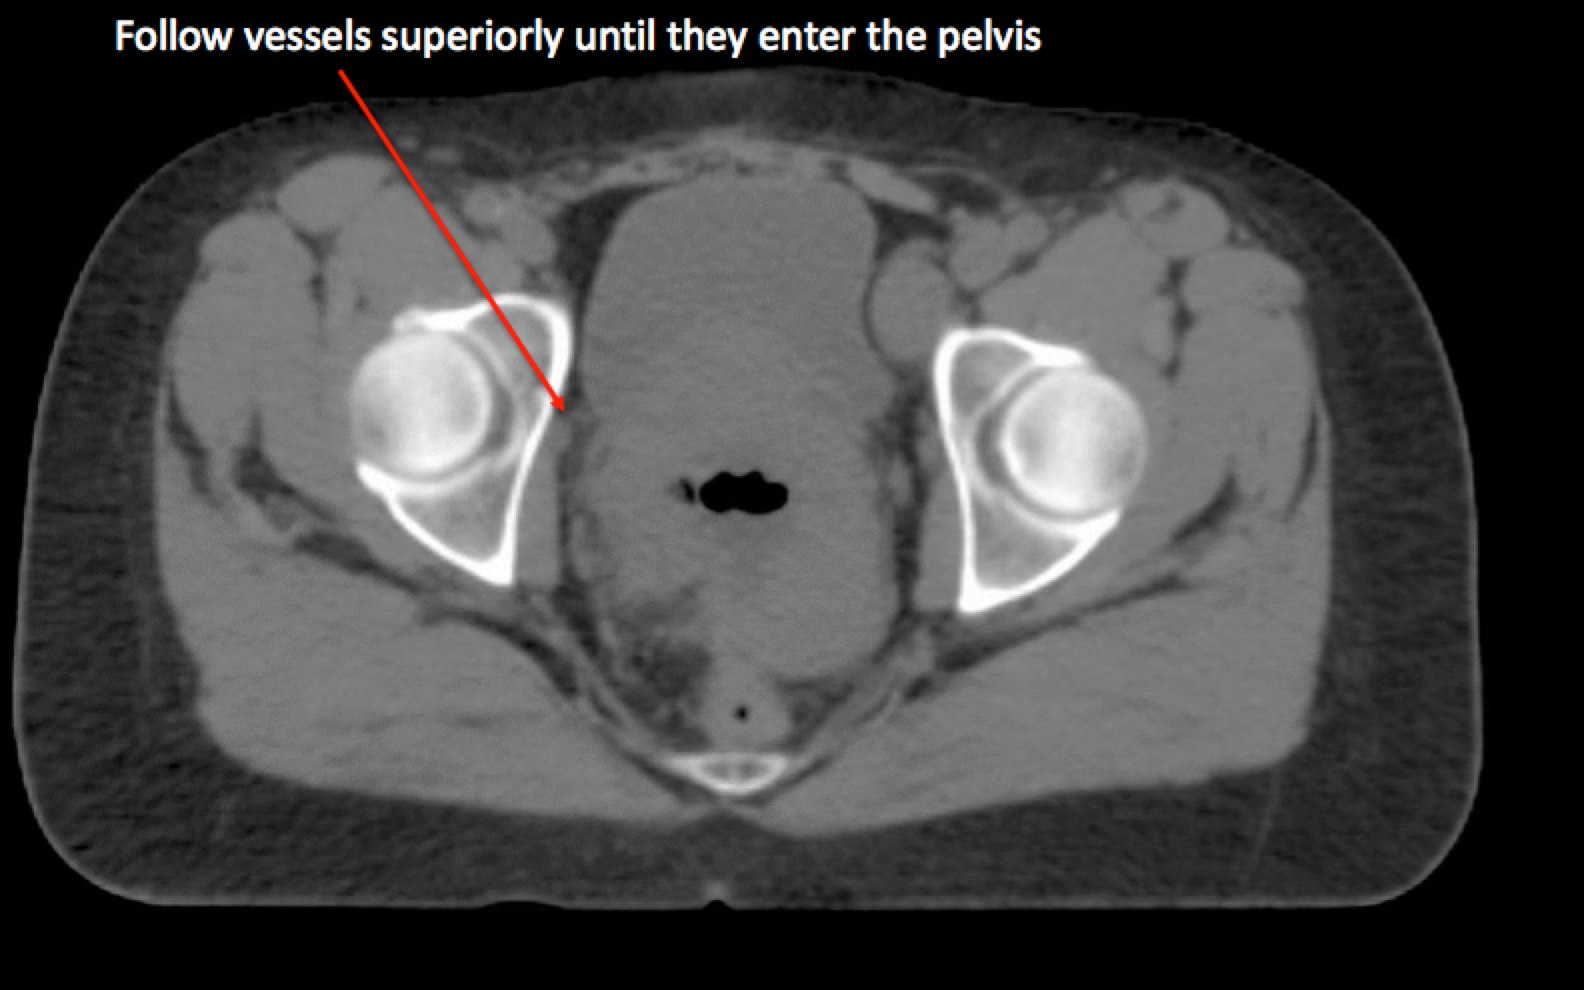

To identify the obturator nodes the following landmarks may be used. (Note: this works for any pelvis where one wishes to find the obturator nodes):

Generally for 3d-CRT treatments, a 4 field technique is used. The upper border for node negative patients is L4/L5. If the pelvic nodes are positive or common iliacs are positive, contour the pelvic nodes and the common iliacs. The upper border is then set at L3/L4. If the para-aortic nodes are positive, use extended field radiation with the upper border set to T12/L1. In this situation, a PET/CT may be very helpful to determine the upper extent of positive nodes. These nodes should be contoured for potential boost radiation. Kidneys and other organs at risk should be identified and shielded. The lateral borders should be 1 cm lateral to the